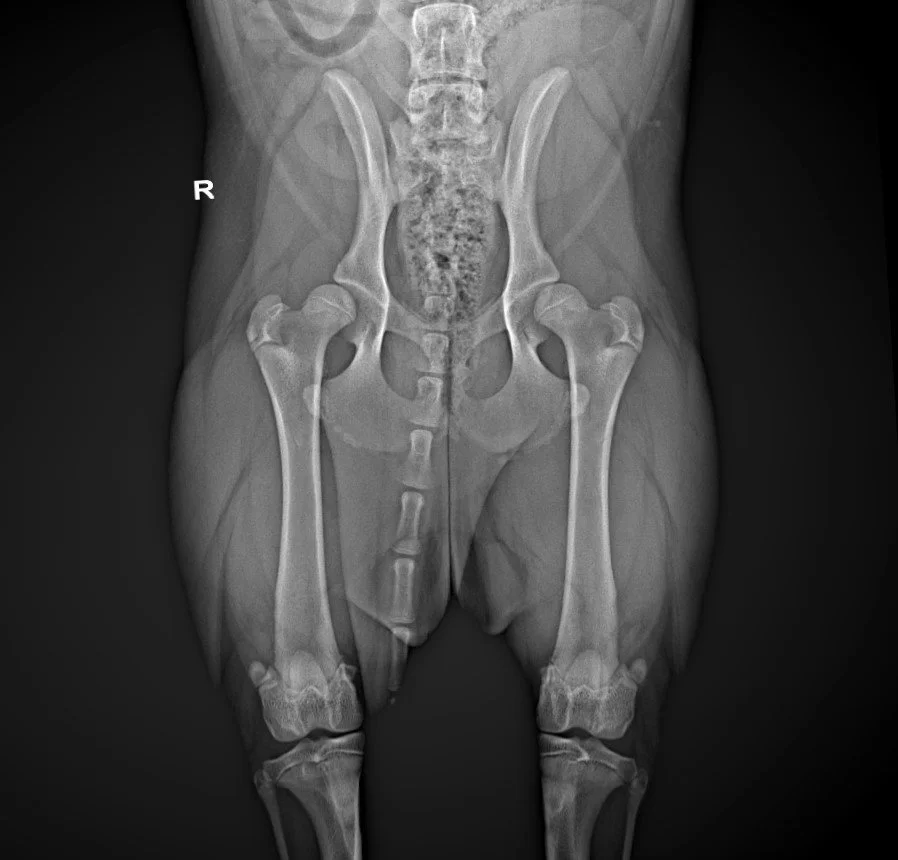

Early Diagnosis of Hip & Elbow Dysplasia in Dogs

Hip and elbow dysplasia are among the most common skeletal orthopedic diseases affecting growing dogs and can significantly impact a dog’s quality of life. They involve malformation of the joints, leading to an imbalanced load distribution within the joint and, consequently, to cartilage erosion, inflammation, and arthrosis.

The first signs of dysplasia can already be detected with certainty at the age of 4 months (5 months in giant breed dogs).

2)      Diagnostic imaging: x-ray under sedation, in some cases combined with CT scan to assess joint conformation minimal joint surface defect (especially in the elbow joint where radiology is indicated for initial assessment but not sensitive enough to confirm the diagnosis).

Large and giant breed dogs are at greater risk to develop dysplasia. For example: the Labrador and the Golden Retriever and their crosses, the German Shepherd, the Rottweiler, the Boxer, the Border Collie, the Newfoundland, the Dogue de Bordeaux, the Cane Corso, and, in general, all molossoids, giant breeds and their crosses.